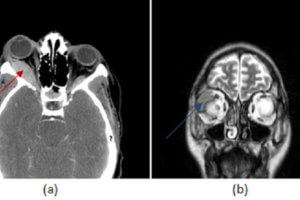

Orbital Lymphoma

The differential diagnosis for an orbital mass is extensive and includes both benign (cavernous hemangioma, sarcoid, varix, meningioma and pseudotumor) and malignant (orbital lymphoma, metastasis, glioma) lesions. Read more »